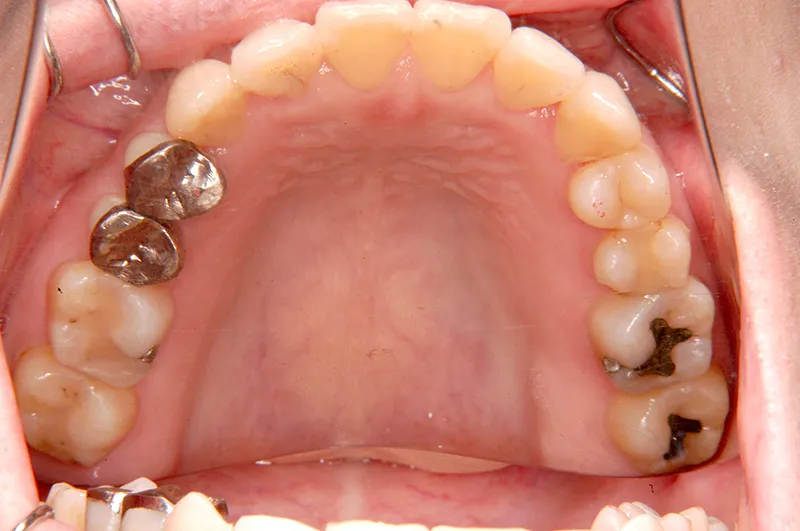

初診時年齢 40歳以上 (女性) 主訴 上下のがたがた・噛み合わない

診断名 叢生 装置名

マルチブラケット装置

歯科矯正用アンカースクリュー

状態 ガタガタ・でこぼこに生えている(叢生)

八重歯(叢生)

上下のがたがたと噛み合わない事を主訴に来院されました。

初診